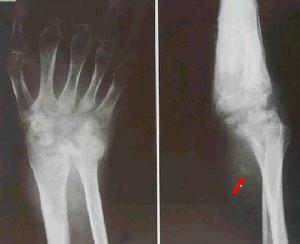

腕關節結核X線表現滑膜型早期可見腕骨小梁模糊,皮質密度變淡,輪廓不完整。晚期由於骨皮質消失及皮質下侵蝕,腕骨可變小。骨型病灶首先開始於橈骨遠端,其次為腕骨(如舟骨、大多角骨、頭狀骨及三角骨),很少繼發於尺骨。病灶常為多發,呈類圓形或不規則形骨缺損,很少有死骨。晚期關節間隙均變窄,病變嚴重者可侵及第2、3掌骨基底部,甚至可達骨幹,可伴有輕度骨質增。生及骨膜反應。病骨往往呈膨脹改變。腕骨結核常合併腱鞘結核,有時可見斑點狀鈣化。兒童的腕關節結核,患側化骨核出現較早。

X線攝片,早期單純滑膜結核,可見骨質疏鬆和軟組織腫脹。尺橈骨下端結核可有死骨中心型和溶骨性破壞的邊緣型。晚期可見多個腕骨尺,橈下端和掌骨關節面廣泛破壞。腕關節出現畸形。

類風濕性關節炎常對稱性侵及多個關節,主要累及滑膜及軟骨,表現為骨質疏鬆,關節面糜爛及小囊狀骨缺損,多出現在骨的邊緣。嚴重者,腕關節可半脫位向尺側偏斜。晚期腕關節強直和肌肉萎縮。